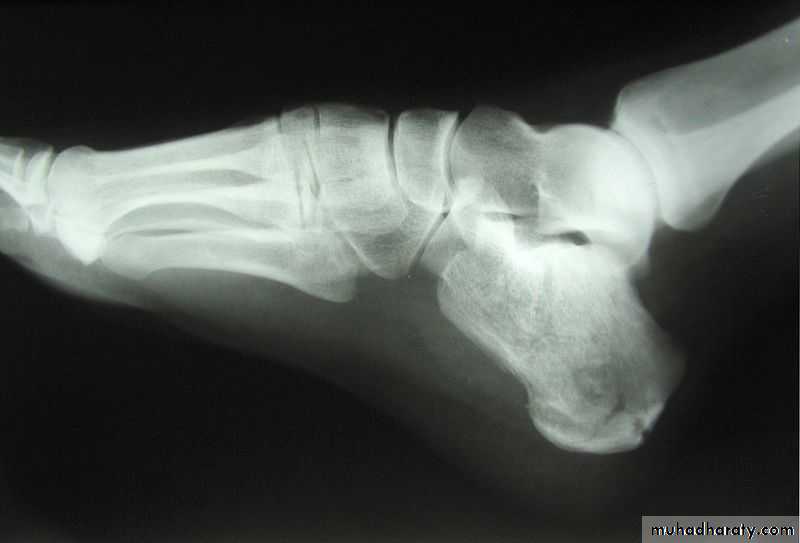

March fracture, also known as fatigue fracture or stress fracture of metatarsal bone, is the fracture of the distal third of one of the metatarsals occurring because of recurrent stress.

Jones fracture is a fracture in the meta-diaphyseal junction of the fifth metatarsal of the foot